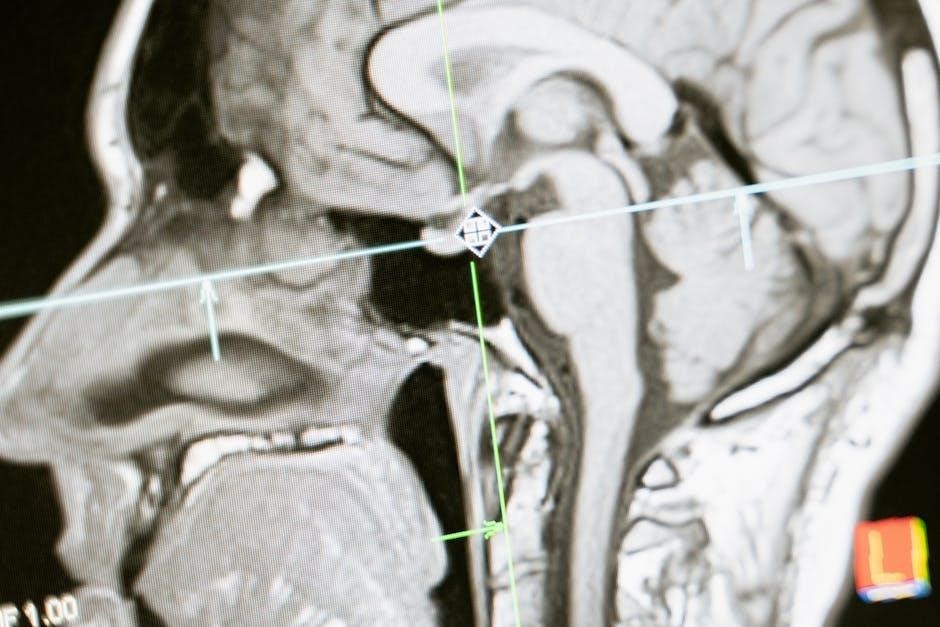

Functional Changes: Altered Brain Activity

Beyond structural alterations‚ addiction profoundly impacts how the brain functions‚ leading to measurable changes in brain activity even in the absence of drug exposure. Neuroimaging studies consistently demonstrate reduced activity in the prefrontal cortex‚ impairing executive functions like planning‚ decision-making‚ and self-control.

Conversely‚ heightened activity is often observed in reward-related brain regions‚ such as the nucleus accumbens‚ contributing to intense cravings and compulsive drug-seeking behavior. This imbalance reinforces the addictive cycle.

These functional changes extend to altered connectivity between brain regions‚ disrupting communication and contributing to cognitive deficits. The brain becomes increasingly focused on obtaining and using the substance‚ at the expense of other important functions.

Addiction neuroscience is rapidly evolving‚ demanding continued investigation into the complex interplay between brain function‚ genetics‚ and environmental factors. A key area of focus is personalized medicine – tailoring treatment strategies based on an individual’s unique neurobiological profile and addiction history. Advanced neuroimaging techniques‚ like fMRI and PET scans‚ will play a crucial role in identifying biomarkers predictive of treatment response.